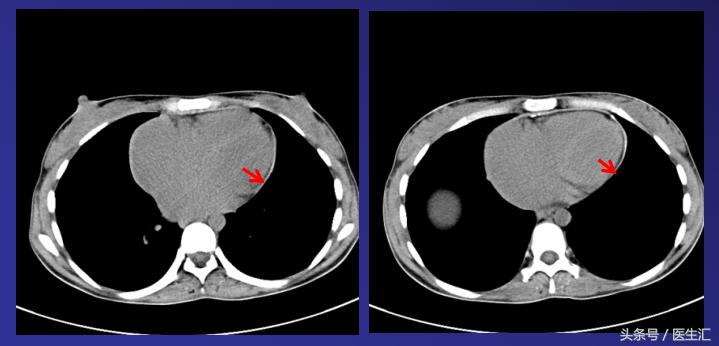

2011-11-18胸部CT:双房增大,心包均匀增厚,可见明显钙化灶,考虑缩窄性心包炎。